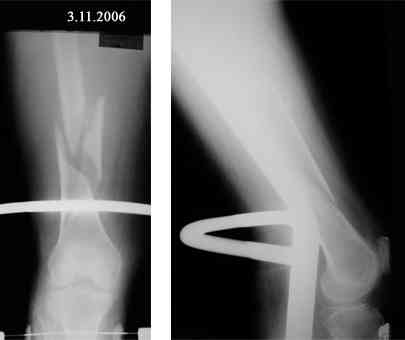

Представляю вашему вниманию снимки в динамике

Закрытый АВФ в этой ситуации может решить Ваши проблемы. Главное не размещать в проксимальном отделе бедра спицевую опору. Чаще всего именно там возникают воспалительные осложнения. Выход: либо "опустить" проксимальную опору к перелому, либо сделать ее стержневой. Срок фиксации правда 3 - 4 мес. На операции после восстановления оси отломок желательно "пришить" сквозной спицей с упором или консольной спицей.

Аппарат вполне для пожилых применим, и даже в классическом спицевом варианте, докторская диссертация Сергея Ивановича Шведа из Курганского РНЦ этому посвящена. Так что на любом этапе можно,

конечно, и аппарат наложить. Хотя бы сразу активизровать пациентку можно будет, и улучшить положение отломков.